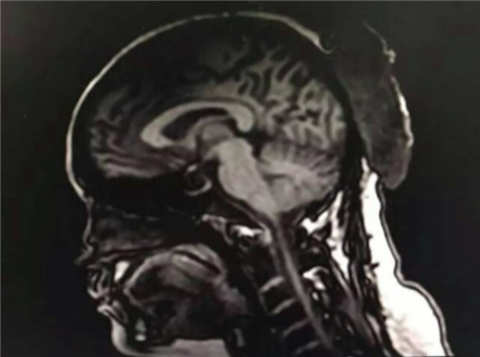

蘇大附一院感染科副主任趙衛(wèi)峰表示,喻先生患上了敗血癥,出現(xiàn)了嚴(yán)重的顏面部感染,并且伴隨敗血性肺炎。這種癥狀嚴(yán)重的話(huà)會(huì)導(dǎo)致顱內(nèi)感染,病情很危重,死亡率很高。

敗血癥又稱(chēng)膿毒血癥,是由于細(xì)菌或者病毒侵入血循環(huán),并在血液中生長(zhǎng)繁殖,產(chǎn)生毒素而發(fā)生的急性全身感染。醫(yī)生說(shuō),從鼻子、嘴唇到下巴,是典型的“危險(xiǎn)三角區(qū)”,毛細(xì)血管密集。喻先生將痘痘擠破以后,細(xì)菌從毛細(xì)血管侵入,從而引起嚴(yán)重感染。目前,喻先生仍然在調(diào)節(jié)當(dāng)中。